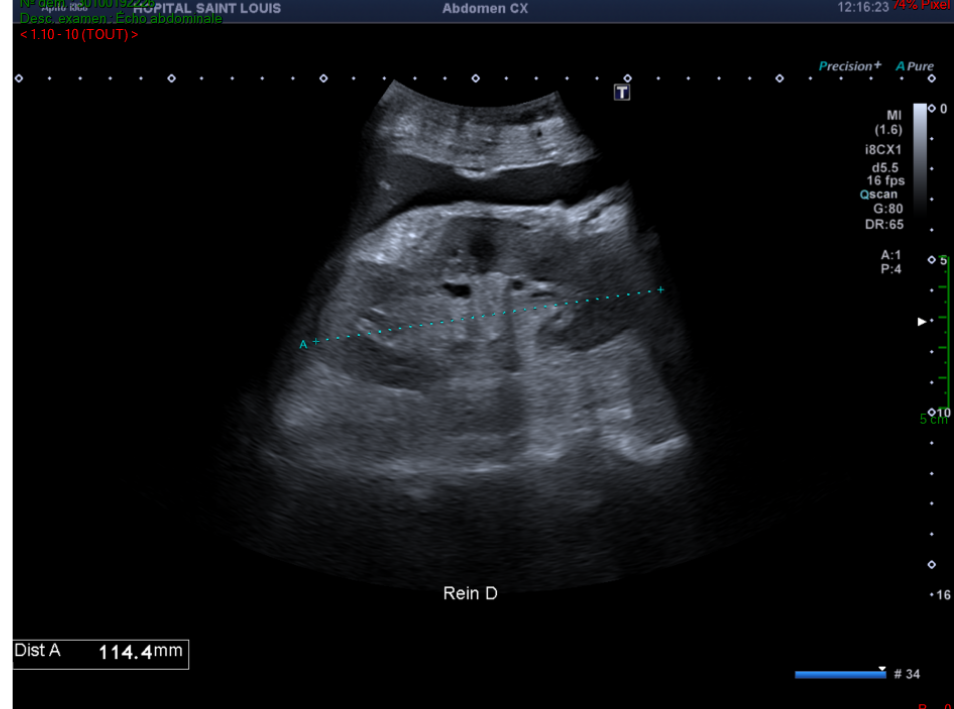

Une échographie abdominale est réalisée chez un patient se présentant pour un bilan de cholestase et un ictère cutanéo-muqueux. Il n’a pas d’antécédent hépatique connu et ne présente pas de douleur abdominale.

Par contre le foie est augmenté de taille de façon harmonieuse.

Hépatomégalie